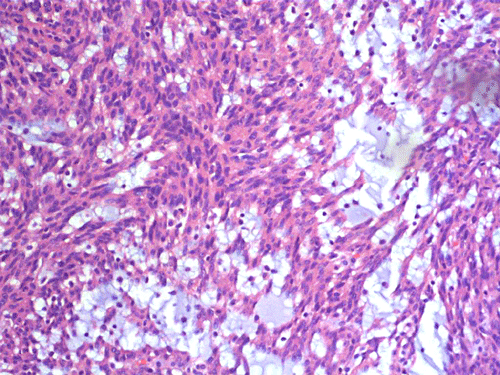

Two major patterns are revealed. In the first pattern, the tumor cells grow in a densely packed tubular pattern with mucinous content (Panel A and B). In some other areas, the tubular pattern is replaced by interlacing fascicles of spindle cells separated by mucinous pools (Panel C and D). In some areas, the spindle cells are solidly packed (Panel E). In both areas, the nuclear are bland in appearance and without significant mitotic acivity. The tumor cells, both in the spindle cell area and tubular areas are strongly positive for cytokerain AE1/AE3, cytokeratin 7, Cam5.2, and epithelial membrane antigen (EMA) respectively (Panel F, G, H and I). The tumor cells are also negative for synaptophysin (Panel J and K) and CD10 (Panel L and M). The positive cells in Panel M are residual non-neoplastic renal tubules. The Ki67 labeling (Panel N) is low (about 1-2%).

| DIAGNOSIS: Mucinous tubular and spindle cell carcinoma. |

These tumors have very characteristic histologic patterns comprised of cuboidal and spindle cells. The cuboidal cells tend to form tubular growth patterns, although trabercular and solid patterns can be identified. Sheets of spindle cells often intersperse between interconnecting tubules, leading to a biphasic appearance. The cells are characterized by eosinophilic cytoplasm, small to medium sized nuclei with little to no atypia, and occasional prominent nucleoli. The surrounding stroma is predominantly myxomatous with a bubbly quality and stains consistently with alcian blue. Studies have shown that a wide majority of MTSCC tumors are positive for epithelial membrane antigen (EMA), AE1/AE3, and cytokeratin 7. In contrast to the classic type of renal cell carcinoma, only about 15% of these tumors are positive for CD10 5. Expression of neuroendocrine markers has also been demonstrated in some tumors 6, 7. Other immunohistochemical markers may be variably positive, including E-cadherin, vimentin, and Ulex Europeus agglutinin-1 (UEA-1). These tumors have a low MIB-1 labeling index. In general, there is not a single marker that could confidently separate this tumor from other renal tumor. The final diagnosis must rest on considerations of morphological and immunohistochemical evidence.